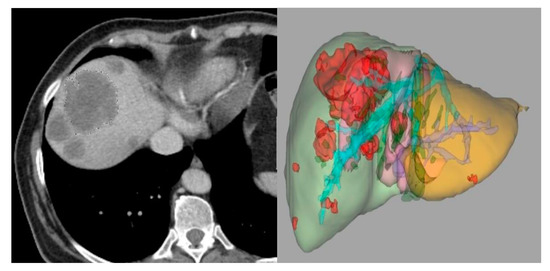

The application of CAD and radiomics to dual-energy X-ray imaging has not been adequately studied. Dual-energy chest radiography and more recently dual-energy or spectral CT have become commercially available and are routinely employed at many large medical centers. Advances in spectral CT are anticipated with the recent commercial introduction of photon counting CT. As illustrated in Figure 6 and Figure 7 dual energy chest radiography permits one to obtain a conventional digital chest radiographic image as well as additional subtraction images with the bones removed (soft tissue image) and with the soft tissue structures removed (bone image). With this capability, the radiologists’ ability to detect subtle pulmonary nodules improved as well as their ability to discriminate between benign and malignant lesions [124,125]. It is anticipated that spectral imaging will also improve the power of CAD and Radiomics when applied to three or more distinctly different images of the same anatomical structures rather than to a single image. Dual-energy or spectral imaging compared to conventional single-energy X-ray imaging also provides reliable quantitative information that could be used to reduce false positives. It is likely that Radiomics will also benefit from the accurate and reproducible quantitative input that spectral x-ray imaging provides.

Figure 6.

Images obtained on a prototype dual energy digital chest radiographic unit at the University of Alabama Birmingham circa 1985 with a single exposure: the conventional digital image was obtained by adding the low and high energy images (left); soft tissue image (center) and bone image (right) [124,125].

Figure 7.

Images obtained on a prototype dual energy digital chest radiographic unit at the University of Alabama Birmingham circa 1985 with a single exposure of a patient with lesions present in both sides of the lung in the conventional digital image (left); Soft tissue (center) and bone (right) images of the patient. The nodule in the lung left side is calcified and benign. The nodule on right side is present in the soft tissue image and not in the bone image, was not calcified and was cancer [124,125].